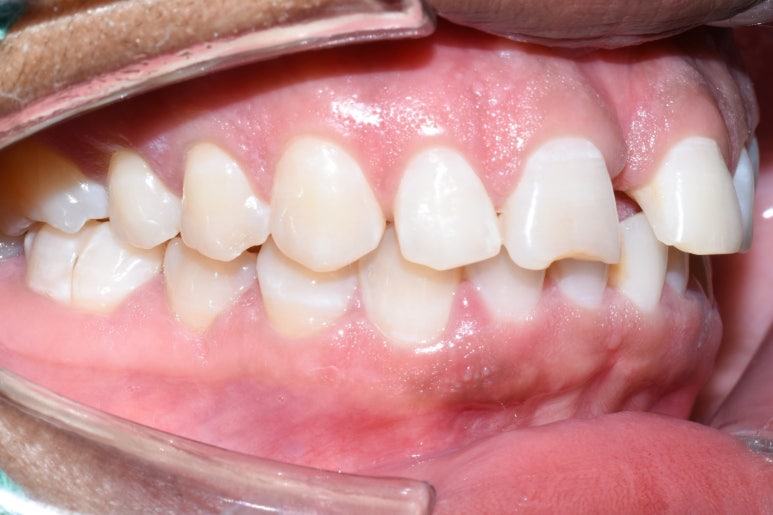

치료전 사진

이 외국인 환자분은 라미네이트를 생각하고 오셨는데요

워낙 앞니 사이 공간이 크고 치아가 뻐드러져 있어서

그냥 바로 라미네이트 치료를 하는 경우에 치아 사이 공간을 메우는 라미네이트가 너무 커져서

앞니 2개만 굉장히 커져 보일 수 있기 때문에

부분 교정을 하고, 라미네이트 4개를 하는 것으로 치료계획을 상담하였습니다.

부분교정을 해도 치아 모양은 변하지 않기 때문에 환자분이 깨진 앞니 치아를 더 예쁘게 만들고 싶어하셔서

라미네이트를 원하셨습니다.